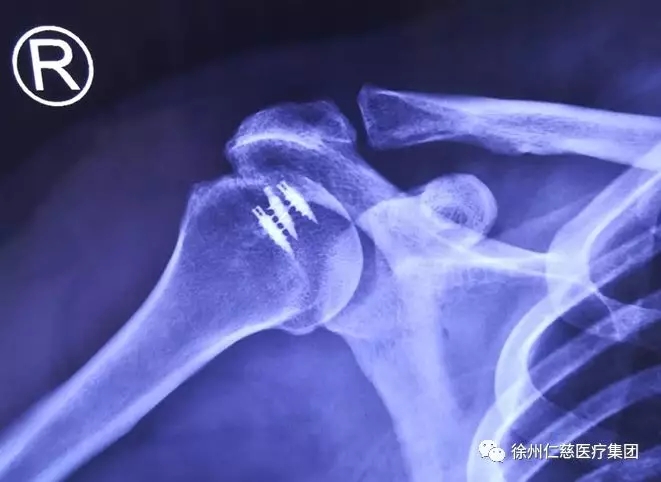

术后片

术中,手术小组注意避免损伤手术部位周围的重要血管神经,减少术中出血,术后予以预防感染消肿等对症治疗。倪大姐因为患2级高血压,手术前医生让她卧床休息,予以低盐低脂饮食、监测血压等对症治疗,一周后才实施手术。